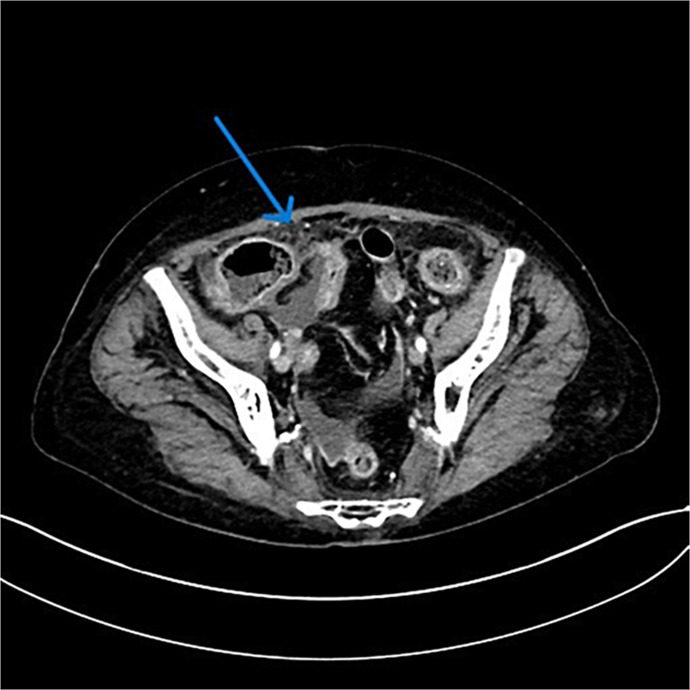

Case presentation: Although VPF mainly occurs as an early postoperative complication of gynecological surgery, we report a case of a 71-year-old female patient who presented with ascites, pseudo-renal failure, and peritonitis caused by a VPF as a delayed complication of radiotherapy.

Conclusion: In this case report, we discuss treatment strategies based on previously published case studies and our experience. We provide a diagnostic overview of commonly available imaging techniques, such as computed tomography scans and magnetic resonance imagings. Despite their widespread use, these imaging modalities have not led to any shift in the diagnostic process, with the definitive diagnosis being confirmed only by retrograde cystography.